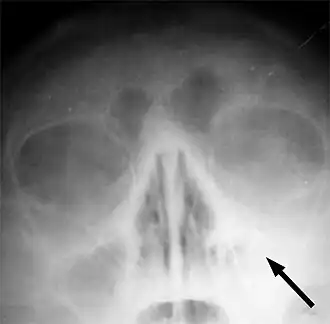

![]() Рентгеновский снимок пазух больного гайморитом (стрелкой обозначено затемнение в области верхнечелюстной пазухи, указывающее на присутствие в ней жидкости) | |

Одним из основных симптомов гайморита является тянущая боль, которая возникает при наклоне туловища вперёд. Подтверждение диагноза производится на основании рентгеновского снимка.

Диагностика синуситов